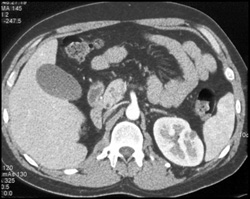

Renal and Pancreatic Cysts